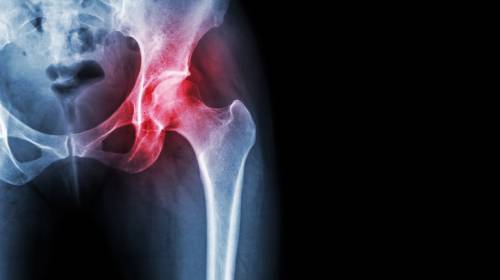

髖關(guān)節(jié)炎是如何引起的?【廣東高尚醫(yī)學(xué)影像】

髖關(guān)節(jié)屬于杵臼關(guān)節(jié),是由股骨頭和髖臼相對(duì)構(gòu)成,多為軸性關(guān)節(jié),能作屈伸、收展、旋轉(zhuǎn)等運(yùn)動(dòng),但由于關(guān)節(jié)頭和關(guān)節(jié)窩之間的面積差不大,運(yùn)動(dòng)范圍較小,且關(guān)節(jié)囊較厚,限制關(guān)節(jié)運(yùn)動(dòng)幅度的韌帶又比較有力,因此髖關(guān)節(jié)雖有強(qiáng)穩(wěn)固性,但靈活性卻較差,因此在髖關(guān)節(jié)運(yùn)動(dòng)時(shí),若有外力作用于膝關(guān)節(jié),就容易導(dǎo)致髖關(guān)節(jié)后脫位。當(dāng)髖關(guān)節(jié)面長(zhǎng)期負(fù)重不均衡,關(guān)節(jié)軟骨就會(huì)產(chǎn)生變性(或產(chǎn)生骨質(zhì)結(jié)構(gòu)改變),這就是髖關(guān)節(jié)炎。

X線篩查對(duì)髖關(guān)節(jié)炎的判斷:

1. 早期影像顯示髖關(guān)節(jié)周圍軟組織腫脹,密度增加,關(guān)節(jié)間隙增寬。

2. 中期影像顯示為關(guān)節(jié)軟骨遭破壞,關(guān)節(jié)間隙變窄,關(guān)節(jié)面骨質(zhì)出現(xiàn)糜爛破壞。

3. 后期影像顯示化膿病變從關(guān)節(jié)囊韌帶附著處入侵骨內(nèi),骨內(nèi)形成膿腫。